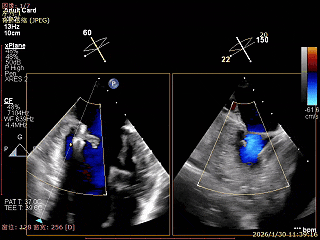

术前超声评估

经胸超声报告提示:患者二尖瓣2区及3区前叶关闭时脱入左房,二尖瓣重度反流(MR 4+),患者LA前后径约52mm,LVEDD约68mm,LVESD约42mm,EF值:65%,经胸超声测二尖瓣瓣口面积约6.1cm2,主动脉瓣无冠瓣脱垂并中重度反流,三尖瓣中度反流,估测中度肺动脉高压。

经食道超声精细化测量:肺静脉逆流,房间隔可穿刺高度约4.2cm,Flail宽度约21mm,Flail高度约8mm,Flail Gap约4mm, 3区AML长约23mm、PML长约12mm、2区AML约32.2mm,PML约16mm。

Bicomm切面看2区脱垂

上Color,可见反流主要来自于3区

X-Plane切面切1区未见明显异常

1区上Color,未见反流来源

X-Plane切面切2区可见前叶Flail

2区上Color,可见反流来源

X-Plane切面切3区可见前叶脱垂

3区上Color,可见反流来源

3D Enface 2区及3区前叶脱向左房

3D Enface 可见反流由2区3区从前后冲出

房间隔可穿刺高度约4.2cm

Flail宽度约21mm,Flail高度约8mm

经胸短轴测得瓣口面积约6.1cm2

3区前叶长度约22mm,后叶长度约11.6mm

2区前叶长度约32.2mm,后叶长度约16mm

2区Flail Gap约4mm